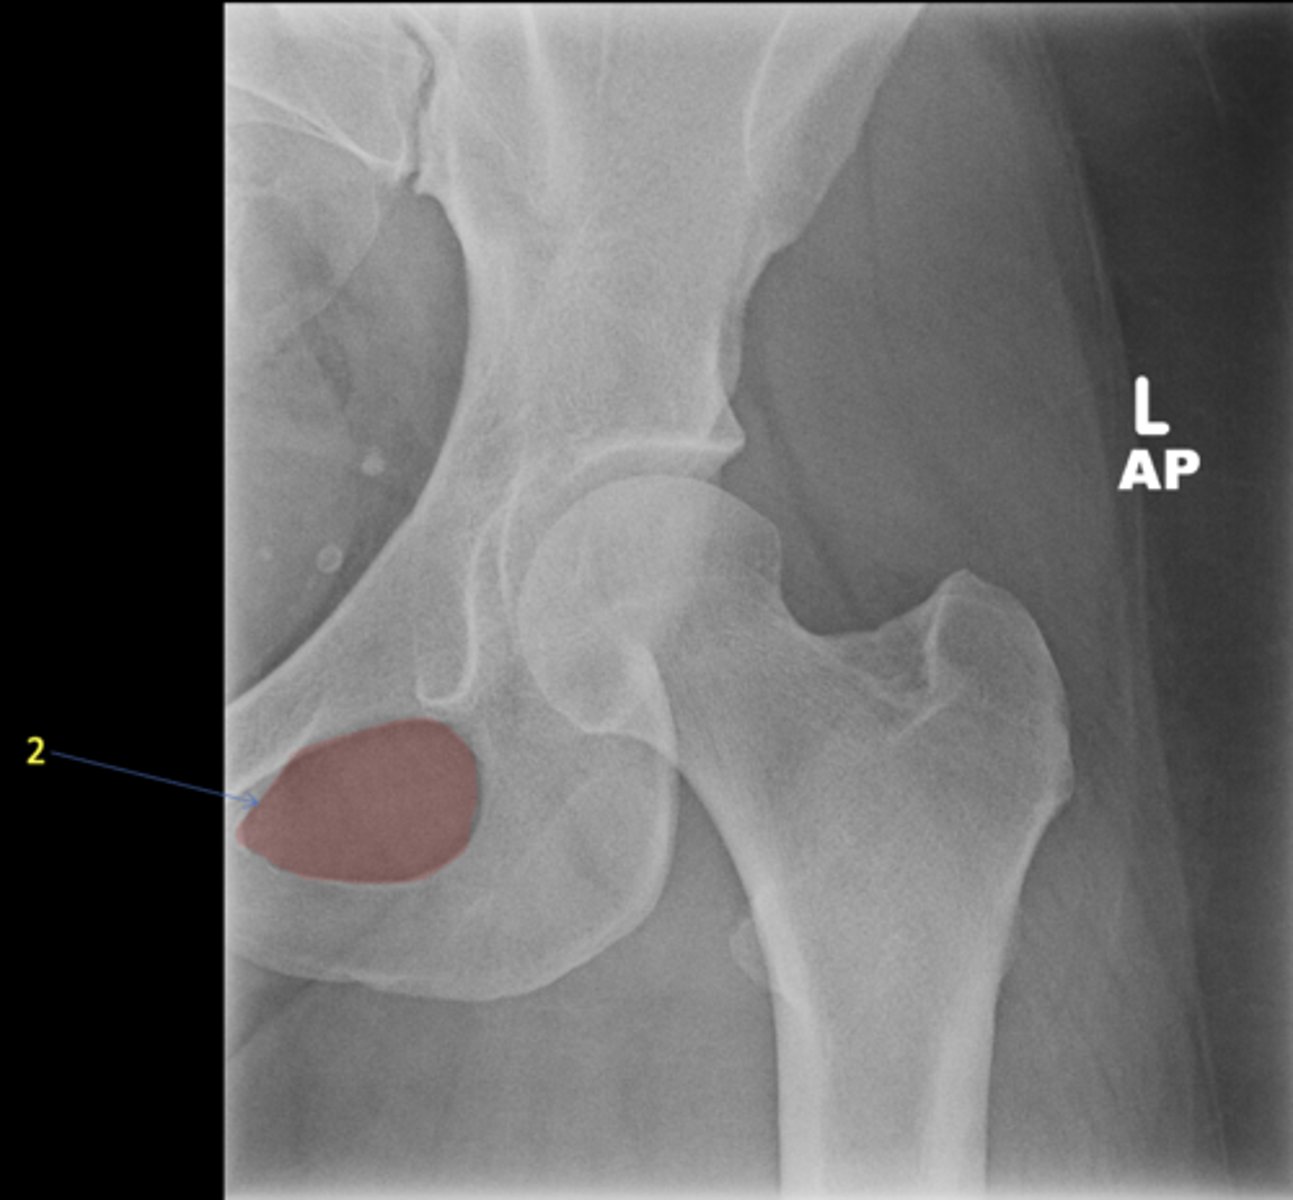

2

Right lesser trochanter

ID 2

<p>ID 2</p>